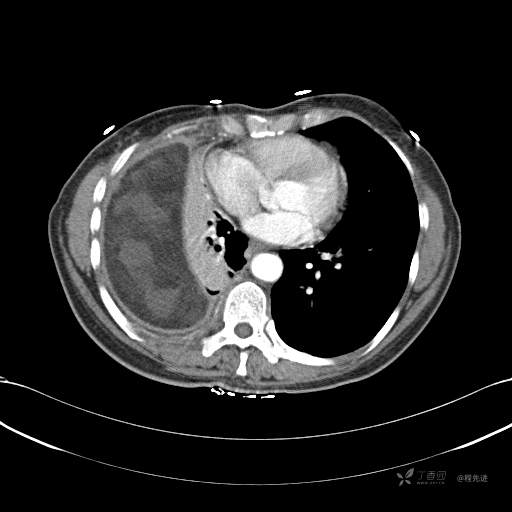

患者性别:女

患者年龄:51岁

简要病史:胸闷半年